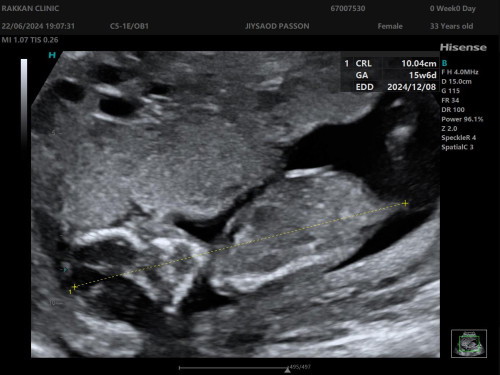

แม่ทรายเพศน้อง ตอนอายุครรภ์กี่สัปดาห์ กันบ้างค่ะ

ทางนี้ 16wแข็งแรง ตามเกณฑ์ แม่ลุ้นเพศน้อง😅